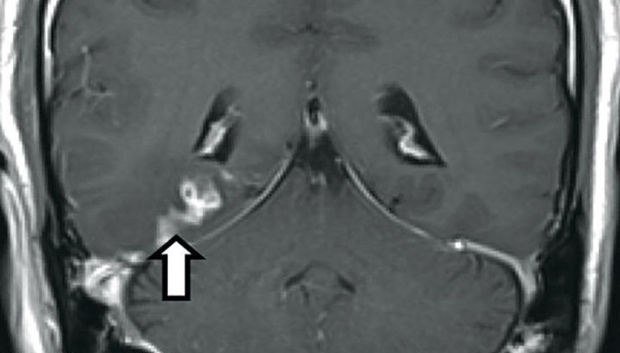

Müayinədən sonra onun beynində dörd santimer uzunluğunda bir cisim aşkar edilib.

Testlərdən sonra bu cismin şiş olmadığı müəyyən edilib.

Növbəti təhlillər bu cismin lentşəkilli qurd olduğunu dəqiqləşdirib.